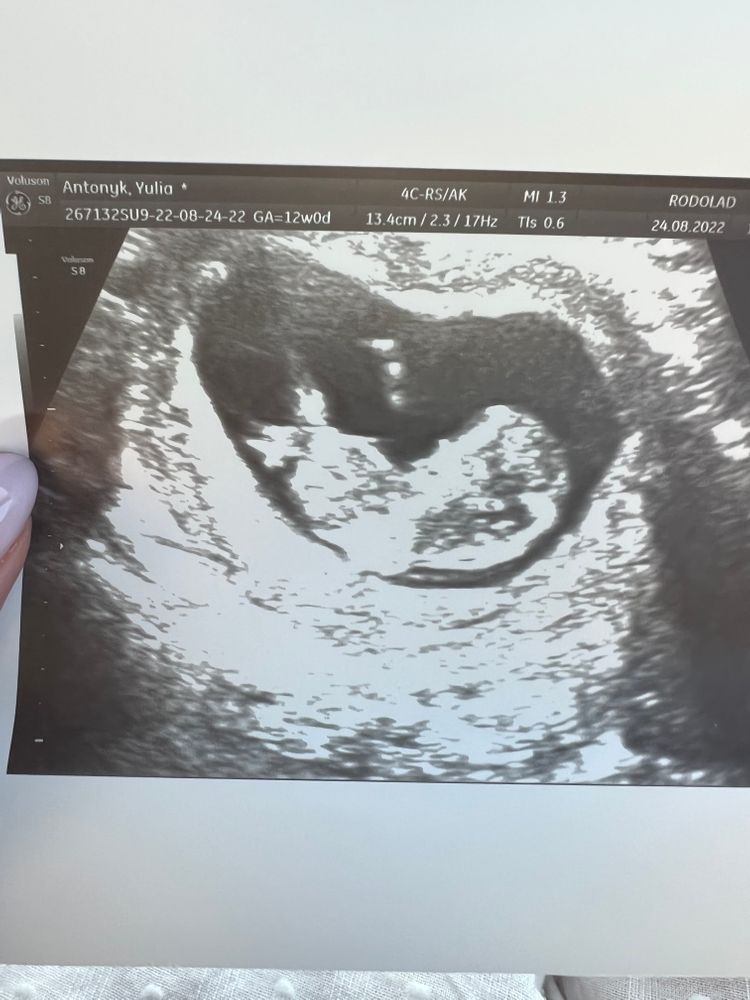

Первый скрининг в 12 недель 🥰

Как же я волновалась перед первым скрининговым узи. Но все хорошо🥰 Малыш подрос и показывал мне танцы. Это так мило, я просто в восторге от нашей встречи ❤️

Ктр - 52мм

Бпр - 17,1 мм

Ож - 51,5 мм

Воротниковое пространство - 1,1 мм

Носик на месте.

Чсс - 143 ( немножко меня смутил этот показатель, ведь по таблице должно быть немного выше. Но врач ничего не сказала, кроме того, что все хорошо)